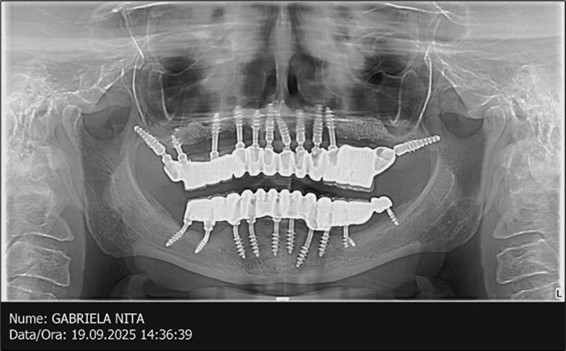

June 2022: Patient presented to our clinic for immediate-loading implant treatment At the time of presentation in 06. 2022, radiologically, advanced peri- implantitis is observed around the implants, with loss of native bone in the affected distal areas (Figure 1)

Figure 1.Panoramic overview picture before rehabilitation 06.2022

Figure 3.Panoramic pictures after removal of implants affected by peri-implantitis, extractions, alveolar crest regularization, and insertion of corticobasal and TPG implants (07.2022)

Figure 15.Follow-up panoramic X-ray 09.2025

Journal of Dentistry and Oral Implants - Periimplantitis

The results of rehabilitation treatment with corticobasal and compressive implants with a polished surface after the failure of two stage implants were highlighted over a period of 3 years and 3 months as being very good (Figure 14, Figure 15), with the patient completing a satisfaction survey in this regard. Certainly, it is necessary to continuemonitoring these results in the long term.